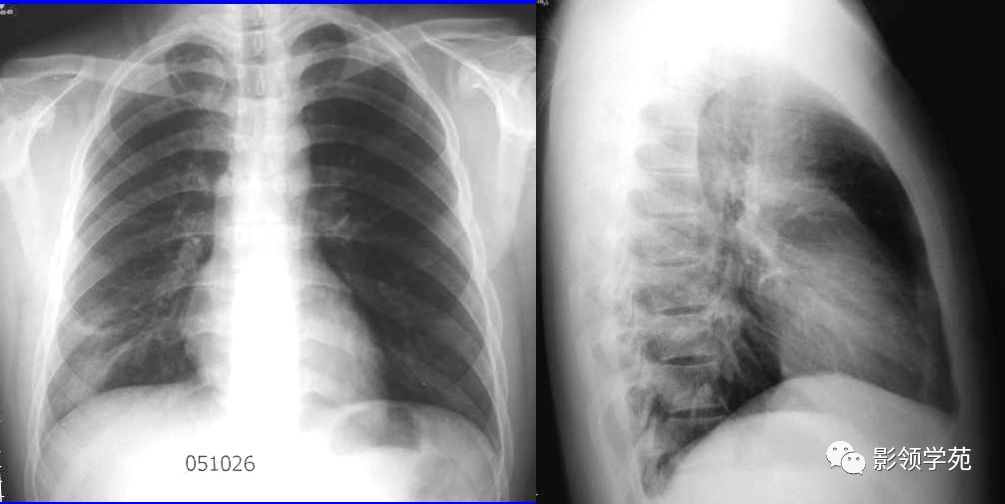

支气管肺炎胸片表现图

支气管肺炎胸片表现图,支气管肺炎胸片

病例 :支气管肺炎.

支气管肺炎胸片

支气管肺炎胸片图解

支气管肺炎胸片特点

支气管肺炎x线表现

支气管肺炎影像图片